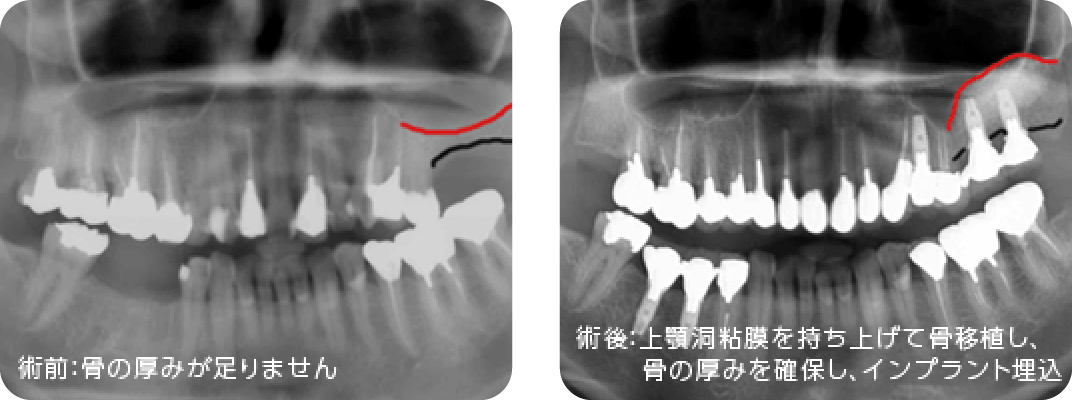

骨造成術

インプラントを埋入するだけの骨がない場合に異種他家骨※1や自家骨※2を移植しインプラントを埋入できるようにします。インプラント埋入と同時に行う場合と、インプラント埋入前に行う場合があります。

※1 異種他家骨は牛骨由来移植材(Bio-Ossやボーンジェクト)を使用しています。狂牛病やヤコブ病など異常プリオン由来の感染の危険性について安全性に問題ないとされており、厚生労働省の承認を得ています。ソケットリフト、サイナスリフトで多く使用します。

※2 自家骨は患者様本人の骨を意味します。当院では下顎臼歯部後方や下顎隆起、口蓋隆起部などから採取しています。インプラント手術部位以外にも手術部位が増えてしまうという欠点がありますが、未知の疾病の感染がないという面において、安全性が高い上、骨誘導能にも優れている利点があります。また、アゴの欠損が大きい方にべニア(オンレー)グラフトができる利点があります。

ソケットリフトとサイナスリフト

上顎臼歯部には上顎洞(副鼻腔の一つ)が存在し、骨の高さが足りない場合があります。その場合、上顎洞底部の洞粘膜(シュナイダー膜)を挙上し、挙上によってできた空隙に骨移植を行い骨造成し、インプラントが埋入できるようにします。当院では骨の高さが5~6mm以上の場合にソケットリフト、5~6mm未満の場合にサイナスリフトを行います。つまり、たくさんの骨移植が必要な場合にはサイナスリフトになります。